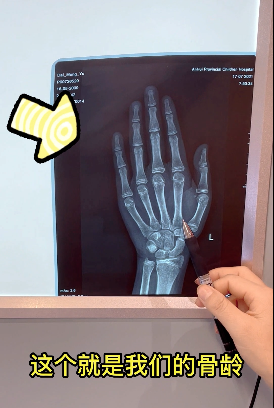

3、依据骨龄精准评价孩子的身高水平

身高停止生长的骨龄具有相对一致性,即男孩骨龄达到16岁、女孩骨龄达到14岁时,身高增长基本趋于停滞。依据骨龄对孩子的身高水平进行评价,更加科学。所以我们提倡家长定期带孩子去医院拍摄骨龄片,进行全面的体格生长评估。